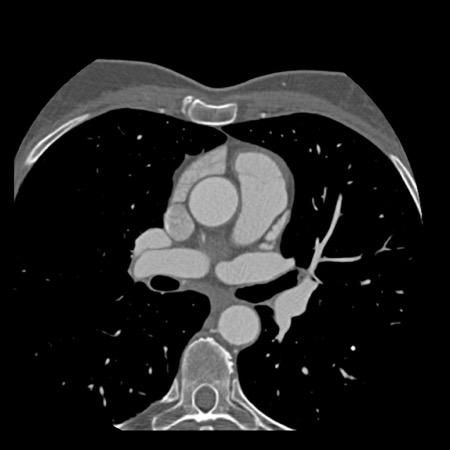

case 1 – CAD-RADS 2/P1

First, scroll through the scan.

Not all images are included. Some images without any abnormalities are skipped

from the series.

How would you describe the findings on the coronary CTA?

The findings are:

- Agatston score of

this patient was 14 (P1). Please, also note the calcification of the aortic valve. - Some partially

calcified and calcified plaques are present in the LAD with mild stenosis

(25-49%). - Calcified-plaque in

the LCX causing minimal stenosis (<25%). - Non-calcified

plaque in the distal RCA causing minimal stenosis (<25%). - This patient classifies

as CAD-RADS 2/P1, which means no further workup is needed.